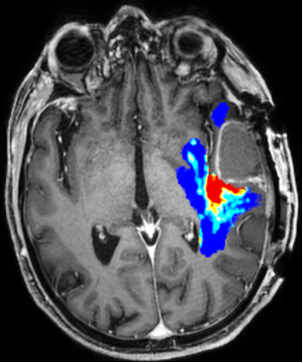

GlioMap is an innovative solution designed to predict areas of infiltration and subsequent recurrence in glioblastoma using radiomic features derived from multiparametric MRI.

This model leverages voxel-wise radiomic features extracted from the non-enhancing peritumoral region of glioblastomas on multiparametric structural MRI. It outputs the probability for each voxel to become a site of future tumor recurrence, visualized through color-coded maps.